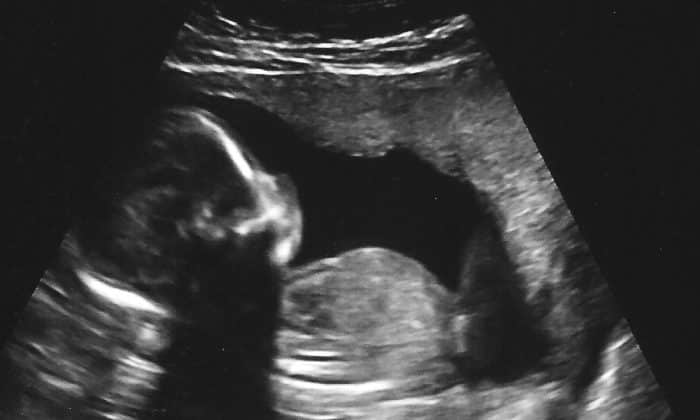

Thông thường thai nhi có tim thai khi bước sang tuần thứ sáu. Luật của bang Mississippi là một trong những biện pháp cứng rắn nhất về chống phá thai tại Mỹ.